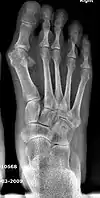

- For recurrence correction after osteotomy procedure (Fig. 8)

Late deformity recurrence can happen after osteotomy (bone-breaking) procedures because osteotomy surgeries do not specifically stabilize first metatarsal bone.